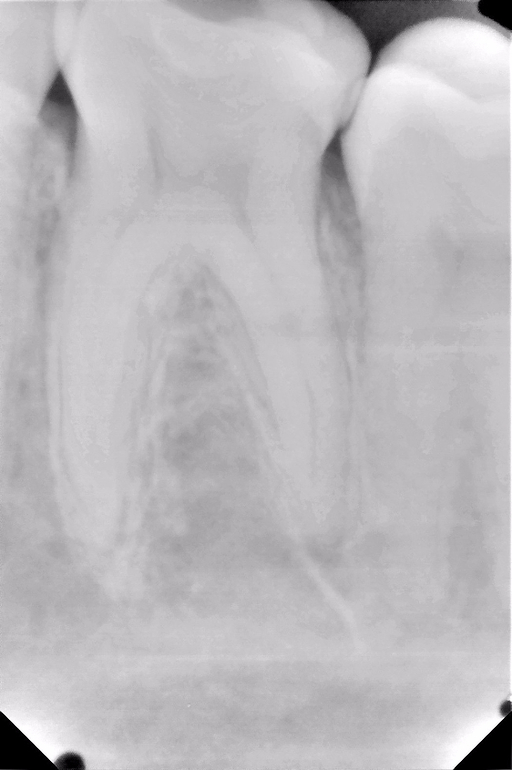

UPD: рентген (прицельный может переделать? на всякий случай панорамный)

Помогите, пожалуйста, определиться с дальнейшей тактикой лечения. Нижняя левая шестерка. Два месяца назад откололся небольшой кусок, поменяли старую пломбу. Потом периодически возникала несильная ноющая боль после твердой пищи, но проходила в течение суток. Оказалась завышена пломба, врач лишнее сточила, промыла карман. После этого появилась практически постоянная ноющая боль (не зависимо от чего-то), чувствительность на холодное, практически не жую на этой стороне. Врач сделала снимок, по ее словам пульпа достаточно далеко от пломбы, зуб в порядке, но глубокий карман. Карман лечили в течении двух недель (йодоформными турундами). По словам врача теперь кармана нет. Но боль продолжается. Собственно, что делать дальше???

может быть поможет вариант поменять пломбу с лечебной и изолирующей прокладкой? Пока динамика положительная, ноет редко и слабо, на холодное все также реагирует, могу немного жевать мягкую пищу. Может быть важный нюанс, между 6 и 7 застряет еда и даже щеткой редко вычищается.